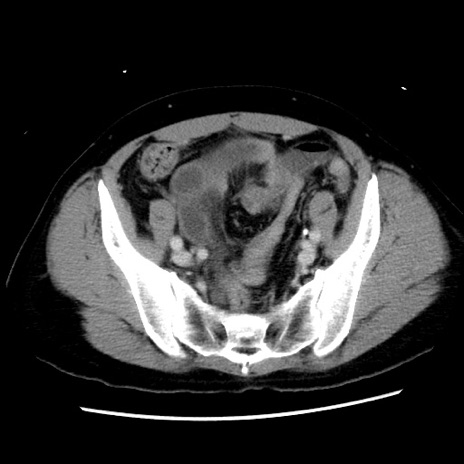

症例10(横断像)

【症例】 50歳代女性

【主訴】 腹痛

【現病歴】前日生レバーを食べた。今朝に排便あり。 昼前に突然発症の腹痛を生じ、当院救急外来を受診した。

【既往歴】 子宮筋腫にてで子宮全摘後

【身体所見】 意識清明、腹部:平坦、軟、下腹部やや左を中心に圧痛・反跳痛あり、筋性防御あり

【データ】WBC 7800、CRP 0.07